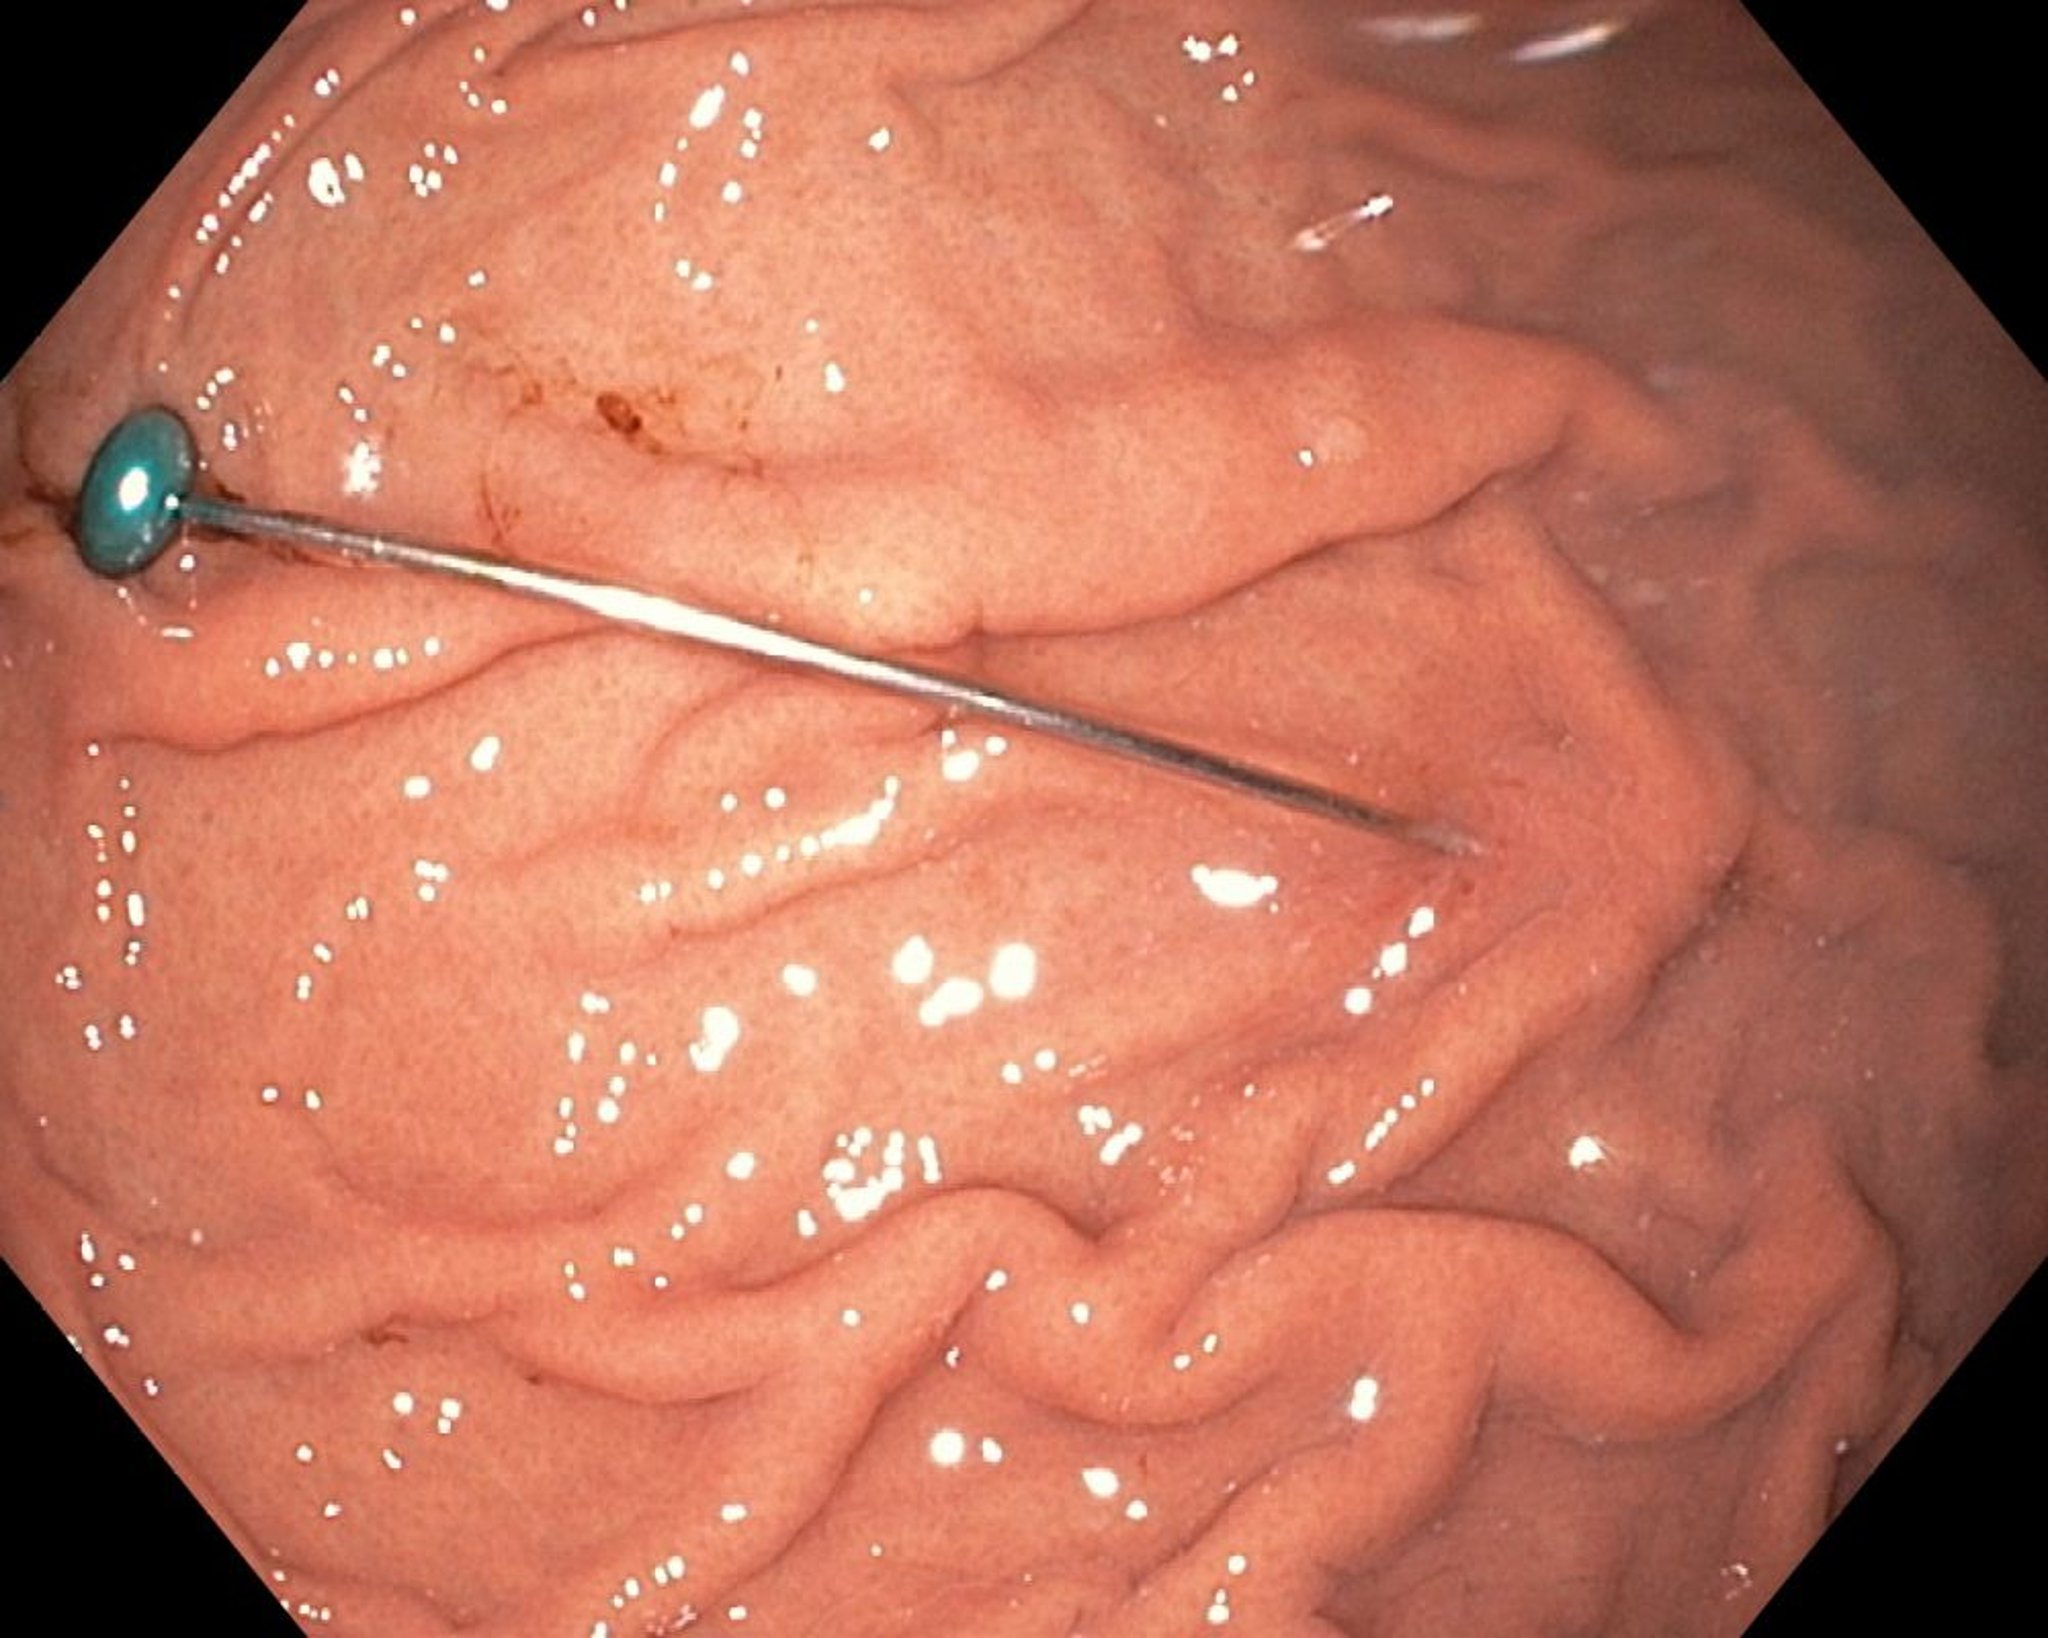

Corpo estranho no estômago (endoscopia)

Essa imagem endoscópica mostra um corpo estranho pontiagudo no estômago.

Imagem fornecida por Uday Shankar, MD.